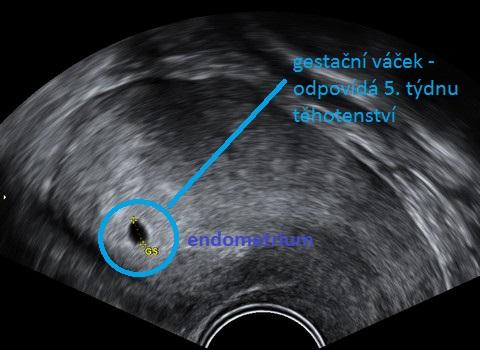

V tomto díle si také vysvětlíme některé pojmy, které v časném těhotenství používáme při popisu ultrazvukového nálezu.

Kavitace – typicky dutinka ve vysokém endometriu, první ultrazvukový obraz potvrzující těhotenství.

GS – gestační váček, je tvořen plodovými obaly a v něm se vytváří embryo.

ŽV – žloutkový váček, vytváří se uvnitř gestačního váčku a postupně na něm lze najít embryonální pól – tedy základ tvořícího se embrya.

V tomto třetím týdnu embrya – tedy pátém týdnu těhotenství – již můžeme na ultrazvuku vidět ve vysoké děložní sliznici dutinku – gestační váček. Těhotenský test bude v tomto období jednoznačně pozitivní.